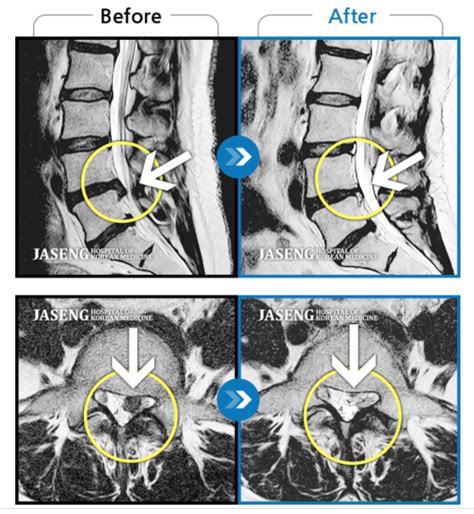

jaseng.ru

Грыжа в пояснице ПОЛНОСТЬЮ рассосалась! Рассказ...